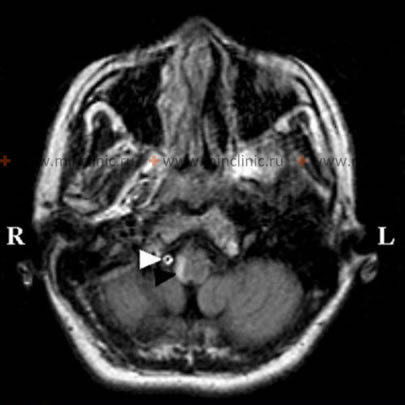

თრომბოზმა (კოლტის წარმოქმნამ) მთავარ დურალურ ვენურ სინუსებში (როგორიცაა განივი/ლატერალური სინუსი ან ზედა საგიტალური სინუსი), ან ზოგჯერ მცირე ზომის კორტიკალურ სადრენაჟე ვენებში, შეიძლება გამოიწვიოს სერიოზული ნევროლოგიური შედეგები [1, 2]. ეს მდგომარეობა, რომელიც ცნობილია როგორც ცერებრული ვენური სინუსების თრომბოზი (CVST), შეიძლება წარმოიშვას სხვადასხვა ძირითადი ფაქტორების გამო[1, 2, 3]:

როდესაც მთავარი ვენური სინუსი ან კორტიკალური ვენა თრომბირდება, ის აფერხებს თავის ტვინიდან ვენურ გადინებას [1, 2]. ამ ბლოკირებამ შეიძლება გამოიწვიოს ვენური შეგუბება და ქალასშიდა წნევის მომატება, რაც იწვევს ისეთ სიმპტომებს, როგორიცაა ძლიერი თავის ტკივილი (ხშირად დიფუზური და მუდმივი), პაპილედემა (მხედველობის ნერვის დისკის შეშუპება), გულისრევა და ღებინება [1, 2]. გარდა ამისა, დარღვეულმა ვენურმა დრენაჟმა შეიძლება გამოიწვიოს ვენური ინფარქტი (ინსულტი ვენური გადინების ნაკლებობის გამო, ხშირად ჰემორაგიული) და ტვინის ლოკალიზებული შეშუპება (ედემა)[1, 2, 4]. ეს პარენქიმული ცვლილებები შეიძლება გამოვლინდეს როგორც ფოკალური ნევროლოგიური დეფიციტი, მათ შორის ფოკალური გულყრები, სისუსტე (პარეზი) ან დამბლა, დაზიანებული ვენური აუზის ლოკაციისა და მასშტაბის მიხედვით [1, 2]. მძიმე შემთხვევებში, რომლებიც მოიცავს ვრცელ თრომბოზს და დიდ ვენურ ინფარქტებს მნიშვნელოვანი მეორადი შეშუპებით, ქალასშიდა წნევის შედეგად მიღებული მატება შეიძლება იყოს სიცოცხლისათვის საშიში, რამაც პოტენციურად შეიძლება გამოიწვიოს კრიტიკული შუა ხაზის ცდომა ან ტვინის ღეროს ჩაჭედვა ნათხემის კარვის ნაპრალში (incisura), რამაც შეიძლება სწრაფად გამოიწვიოს კომა და სიკვდილი [1].

| ცერებრული ვენური სინუსების თრომბოზი (CVST) | თავის ტკივილი (ხშირად ძლიერი, პროგრესირებადი), გულყრები, ფოკალური ნევროლოგიური დეფიციტები (ცვალებადი, შეიძლება იყოს ორმხრივი/მულტიფოკალური), ICP-ს მომატების ნიშნები (პაპილედემა, VI კრანიალური ნერვის პარეზი), შეცვლილი მენტალური სტატუსი. რისკ-ფაქტორები (ინფექცია, ჰიპერკოაგულაციური მდგომარეობა, ორსულობა, ორალური კონტრაცეპტივები) ხშირად სახეზეა. | MR ვენოგრაფია (MRV) ან CT ვენოგრაფია (CTV) სადიაგნოსტიკოა: ადასტურებს ნაკადის არარსებობას / ავსების დეფექტს (თრომბს) დურალურ სინუს(ებ)ში ან კორტიკალურ ვენებში. თავის ტვინის კონტრასტულმა მრტ-მ შეიძლება აჩვენოს ასოცირებული ვენური ინფარქტები (ხშირად ჰემორაგიული) ან მაგარი გარსის ინტენსიური კონტრასტირება სინუსთან ახლოს. D-დიმერი შეიძლება იყოს მომატებული (მაგრამ არასპეციფიკურია). |